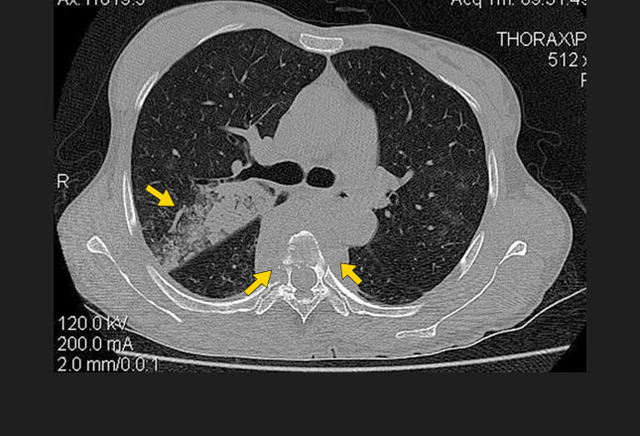

图8. 这张轴面CT来自一位继发性肺结核慢性脓胸患者,展示了其左侧钙化的胸腔积液。

影像学特征包括斑片状或肺叶的实变、空洞(继发性肺结核的典型表现)、纵隔淋巴结肿大和胸腔积液。继发性肺结核常侵犯上叶尖后段及下叶背段。代表着血行播散的粟粒型肺结核并不常见,但预后不佳。